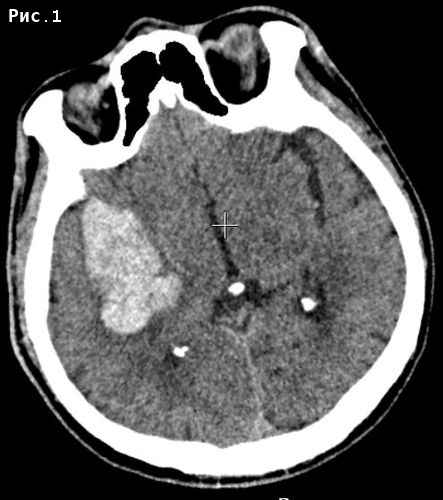

Инсульт удаление гематомы

Инсульт удаление гематомы 108 фотографий